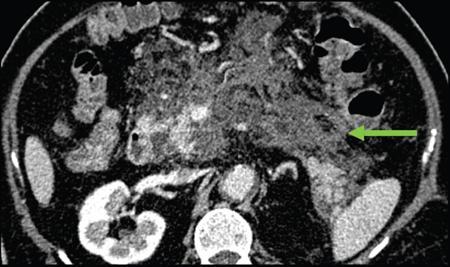

Anirudh Kohli Acute pancreatitis is one of the most dreaded diseases to afflict mankind, in view of its high morbidity and mortality. The single most important factor in reducing the morbidity and mortality of this condition over the last many years has been the role of computed tomography (CT). The incidence of acute pancreatitis is rising especially due to an increasing incidence of gallstones, obesity, as well as an ageing population. Pancreatitis occurs due to a chain of events triggered by a temporary/permanent pancreatic duct obstruction. This leads to activation and release of pancreatic enzymes into pancreatic interstitium and peripancreatic tissues leading to severe auto digestion and necrosis of pancreas and adjacent tissues. Systemically there is release of inflammatory mediators known as cytokines. Tumour necrosis factor is a cytokine which is toxic to acinar cells. These cytokines activate and intensify the inflammatory cascade that may ultimately culminate in multiorgan failure. Clinically severe acute pancreatitis is characterized by two phases, an early phase and a late phase. The early phase is dominated by the systemic effects of release of inflammatory mediators such as cytokines – termed as systemic inflammatory response syndrome (SIRS). Usually there is associated variable multiorgan dysfunction/failure. This phase lasts for a week. When the multiorgan failure lasts 2 days it is termed as mild, multiorgan failure lasting more than 48 hours is considered severe. There is no correlation between the clinical severity of pancreatitis and morphological changes in this early stage. In view of this CT scan is not of much utility during this phase, unless complications are suspected. The later phase is dominated by effects of local complications due to pancreatic/peripancreatic necrosis. Mortality follows this biphasic pattern in early weeks from the systemic effects of multiorgan failure and in later weeks due to local effects, for example infection of necrotic pancreatic/peripancreatic tissues superimposed by organ failure. The Clinical diagnosis of acute pancreatitis requires two of the following three features: If the first two findings are present without any significant SIRS then CT is not required. Acute pancreatitis is a complex disease with a wide variation in the presentation and outcome, ranging from asymptomatic with only biochemical alterations to a fatal outcome. In fact acute pancreatitis is a dynamic disease with continuously evolving appearances on imaging. There are two distinct forms of acute pancreatitis – interstitial oedematous pancreatitis and acute necrotising pancreatitis. Interstitial oedematous pancreatitis is a condition where there is only mild swelling of the pancreas with loss of normal lobulations and a diffuse decrease in attenuation of the pancreas. There may be heterogeneity of the pancreatic parenchyma due to varying degrees of interstitial oedema. This form of pancreatitis runs a mild course and rarely progresses to acute necrotising pancreatitis with its associated complications. In a third of these cases the pancreas may reveal no abnormality on a CT scan. The inflammatory changes may be restricted to the pancreas or extend into the peripancreatic regions. The inflammation in the peripancreatic regions manifests as acute pancreatic effusions. If there is peripancreatic fat necrosis with an oedematous pancreatic gland it is termed as acute necrotising pancreatitis (Figs. 9.17.1–9.17.2). Acute pancreatic fluid collections are enzyme-rich pancreatic juice collections seen in about 40% of patients with acute pancreatitis. The fluid collections occur due to exudation of pancreatic juices into the interstitium of the pancreas and subsequently leakage into the surrounding tissue spaces. These fluid collections are localized only by the anatomic space in which they collect. As the exudative process continues, the parietal peritoneum overlying the pancreas may be disrupted with the inflammatory fluid entering the lesser sac. From the lesser sac the fluid can enter the peritoneal cavity via the foramen of Winslow or by dissecting the peritoneum along the anterior surface of the lesser sac. Posterior extension of the fluid collection in the anterior pararenal space may occur into a potential space between the laminae of the posterior pararenal fascia. Rarely there may be involvement of the perirenal and posterior pararenal spaces. Other pathways of dissection are along the gastrohepatic, gastrosplenic and gastrocolic ligaments. Fluid may dissect along the root of the mesentery into the transverse mesocolon. Collections may extend around the caecum, ascending colon, descending colon and into the lumbar, pelvic and inguinal regions. Large fluid collections may dissect superiorly into the mediastinum or pericardial space. The quantity of fluid in these effusions is variable and can range from a small amount to large quantities (Fig. 9.17.3). Of these collections, 50% resolve spontaneously; the remainder may evolve after 4–6 weeks into pseudocysts. As the collections age, they tend to get localized and walled off, often developing an enhancing wall. A collection should be termed a pseudocyst only when a definite capsule develops and the collection has been static for at least 4–6 weeks. The risk of complications such as rupture, infection and haemorrhage increases with the age of the collection. Large collections of fluid are usually associated with a lesser degree of pancreatic necrosis as compared to extensive pancreatic necrosis associated with a lesser amount of fluid collection. Acute necrotising pancreatitis is a fulminant form of pancreatitis in which there is necrosis of the pancreas, that is nonviable pancreatic tissue. A contrast-enhanced CT is essential as it is the ideal means to demonstrate necrosis as well as to determine the extent of necrosis. These areas of nonviable pancreatic tissue do not enhance as compared to viable pancreatic tissue, which demonstrate significant enhancement. The extent of pancreatic necrosis has been found to correlate extremely well with the extent of necrosis found at surgery. The size, location and extent of pancreatic necrosis are very variable. These areas may be diffuse or focal, small in size to complete glandular involvement. These necrotic areas have a very important bearing on the course of pancreatitis, as they are liable to undergo secondary infection and form pancreatic sepsis. In addition, the more extensive the pancreatic necrosis the greater is the morbidity and mortality. Patients with no pancreatic necrosis have been found to have a 0% mortality and a 6% complication rate, whereas patients with pancreatic necrosis have a 23% mortality rate and an 82% complication rate. A variety of laboratory tests are available to detect pancreatic necrosis, such as a rise in the serum methemalbumin, quantitative estimation of C-reactive protein and urinary trypsinogen-activated peptide. CECT is still the most accurate modality to detect pancreatic necrosis. Pancreatic necrosis may be seen in the pancreas only, peripancreatic tissues also or only in the peripancreatic region. Isolated peripancreatic necrosis occurs due to disruption of the peripheral ductules with extravasation of activated pancreatic enzymes, may be seen in up to 20% of patients who require operative/interventional management of their necrotising pancreatitis. These patients with only peripancreatic necrosis have a better prognosis. This essentially represents retroperitoneal fatty tissue necrosis appearing as heterogeneous areas of liquid and nonliquid components. Over time necrosis evolves and liquefies as well as the liquid component resorbs. Generally if the liquid component is 2 cm or less it will resorb, while fluid collections 5 cm or more rarely resorb. If pancreatic necrosis is not resorbed it may get walled off or with time or may become infected. Encapsulation occurs between the third and fourth weeks. It is important to differentiate sterile from infected necrosis as sterile necrosis rarely needs surgery, whereas infected necrosis requires long-term antibiotic therapy and/or some kind of imaging/surgical intervention. According to the Atlanta 2012 classification, all areas of pancreatic necrosis are termed as acute necrotic collections. This represents a combination of pancreatic/peripancreatic fat necrosis with peripancreatic effusions. On CT, there is a spectrum of findings – solid, liquid containing debris (these may be nonwalled off/partially walled off). Sonography and MRI have advantages over CT scan in demonstration if the contents are pure liquid such as acute pancreatic effusions or have some nonliquefied components such as acute necrotic collections. Pseudocysts are round or oval encapsulated fluid collections containing only liquefied components. It takes 4 weeks for the granulation tissue to develop. On CT, a pseudocyst appears as a well-defined fluid collection with a thin capsule. The most common location for pseudocysts is the lesser sac, though they may be found anywhere in the mediastinum, abdomen or pelvis as they may dissect along fascial planes, along vessels and through capsules of solid organs. Pseudocysts in the bowel, though reported, are relatively rare, as the bowel wall is a strong barrier to the effect of proteolytic pancreatic enzymes. When the contents of the pseudocyst are heterogeneous or uniformly increased in attenuation, the possibilities of infection or haemorrhage should be considered. Focal areas of increased density within the fluid collection usually indicate haemorrhage. Complicated, enlarging or symptomatic pseudocysts require percutaneous catheter or surgical drainage. Infected pseudocysts are treated by percutaneous drainage. The management of a noninfected pseudocyst is controversial. Surgical treatment is only undertaken when the wall is mature after several weeks. Large pseudocysts greater than 5 cm in size can easily be drained percutaneously using intercostal drainage tube or pigtail catheter or endoscopically via the stomach. The cure rates are reported to be 85% with percutaneous drainage, the drainage period averaging about 20 days (Figs. 9.17.4–9.17.5). Walled off necrosis – as pancreatic/peripancreatic necrosis matures and evolves, an interface develops between necrosis and adjacent fatty tissue and an enhancing thickened wall is seen, resulting in a well-defined fluid collection with necrotic debris and fat necrosis. This is the end stage in the evolution of an acute necrotic collection. It is important to differentiate a pseudocyst from walled off necrosis, as a pseudocyst requires drainage and walled off necrosis requires surgical removal (Figs. 9.17.6–9.17.9). Sepsis is a major complication of pancreatitis and is accompanied by a high incidence of mortality and a prolonged hospital stay. Pancreatic sepsis may occur following secondary infection of pancreatic and/or peripancreatic necrosis, acute pancreatic fluid collections and pseudocysts. The only specific sign to demonstrate sepsis is the presence of gas in a collection. This occurs due to secondary infection by coliform/anaerobic organisms. This sign is unfortunately not common and seen in only one-third of cases. Gas is seen in the fluid collection as very dark well-defined air attenuation bubbles. Occasionally gas may be present due to a gastrointestinal fistula or previous surgery. Fat necrosis is seen in peripancreatic collections. This should not be confused with air bubbles, which are indicative of sepsis. The differentiation is easy to understand by CT, the values of fat ranging between – 20 HU and – 80 HU, and of air being >–300 HU. Also air bubbles have well-defined margins and are homogeneously jet black, whereas fat is nonhomogeneously grey with ill-defined margins. Since the presence of air is seen only in a small percentage of patients with pancreatic sepsis, the only other means to diagnose pancreatic sepsis is by CT-guided aspiration. All sites of fluid collection, parenchymal necrosis and peripancreatic necrosis are subjected to CT-guided aspiration. This is a tedious process and requires a dedicated interventional radiologist as there are often more than 5–6 sites from which it may be necessary to obtain samples. A fresh needle and syringe are used for each site, as it is important to know which site has sepsis and which is sterile. Care is taken not to transgress the large bowel as the colon has a large number of bacteria, and transgressing it could result in colonic bacteria contaminating the CT-guided aspiration sample, with falsepositive results. Further, colonic bacteria may be inoculated into a sterile acute pancreatic fluid collection or necrosis thereby converting a sterile collection into an infected one (Fig. 9.17.10). Complications of the procedure can be pneumothorax if the pleura is transgressed, haemorrhage due to trauma to a vessel, and secondary infection. Pancreatic sepsis is treated by surgical debridement, necrosectomy and drainage through thick tubes. It is crucial from the management point of view to differentiate an abscess from infected necrosis. An abscess may be treated by percutaneous drainage, whereas infected necrosis developing in relatively solid tissue can be treated by surgical debridement alone. Imaging-guided percutaneous drainage is the first step in treating pancreatic sepsis especially patients who are very ill and cannot undergo surgery. Initially pig tail catheters were used but these are notorious to get blocked as the largest bore of a pigtail catheter is 12 F. Pancreatic sepsis contains a large amount of necrotic debris, this blocks the catheters can be cleared by flushing the catheter, but this always raises the possibility of introducing secondary infection. To circumvent this issue large-bore ICD catheters have been introduced. These range from 16 F to 30 F. A safe window is necessary, not transgressing bowel or vasculature. It is quite easy to insert these tubes percutaneously under CT. A bit of initial manipulation and force is required to pierce the abdominal musculature. These large-bore drainage tubes have been very effective unless the infected necrosis is solid with minimal liquefied contents or a safe window for placing an ICD catheter is not available. CT is also invaluable in surgical planning and in the follow-up of postoperative patients to evaluate any fresh collection and also to determine whether the drains are well sited or not (Fig. 9.17.11).